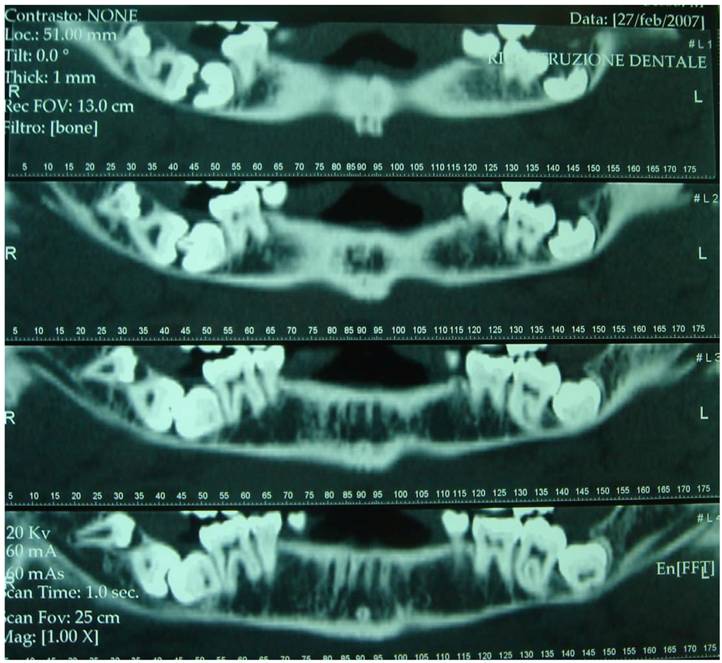

Figure 6

Dental-Scan of the mandibular bone (proband)

In agreement with the international literature, the Authors opted to leave the sisters' supernumerary teeth in situ, as there were not any signs or symptoms justifying the extraction therapy. Whereas the patient who first came to our attention was subjected to extraction of teeth 4.7, 4.8 and 4.9, after a routine hematological investigation and after the assessment of radiographic exams, such as X-Ray Dental Panoramic Tomogram and Denta-Scan (Fig. 6) of the inferior maxillary bone. Exodontia led to remission of the algic symptomathology, without compromising somesthesia in the treated region, although the extracted teeth were in the close proximity of the inferior mandibular canal.